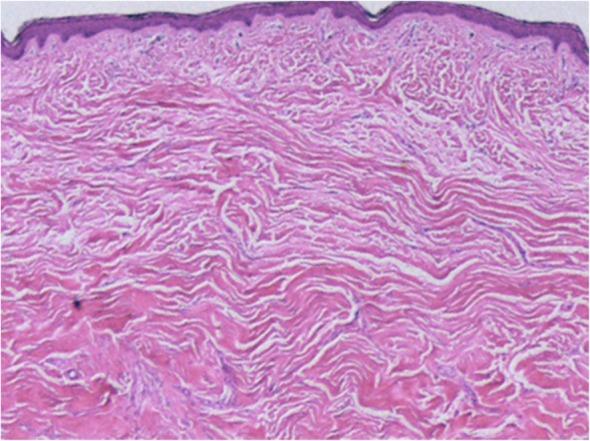

Keloid and Hypertrophic Scars Are the Result of Chronic Inflammation in the Reticular Dermis.瘢痕疙瘩和增生性瘢痕是网状真皮层慢性炎症的结果。

Int J Mol Sci. 2017 Mar 10;18(3):606. doi: 10.3390/ijms18030606.